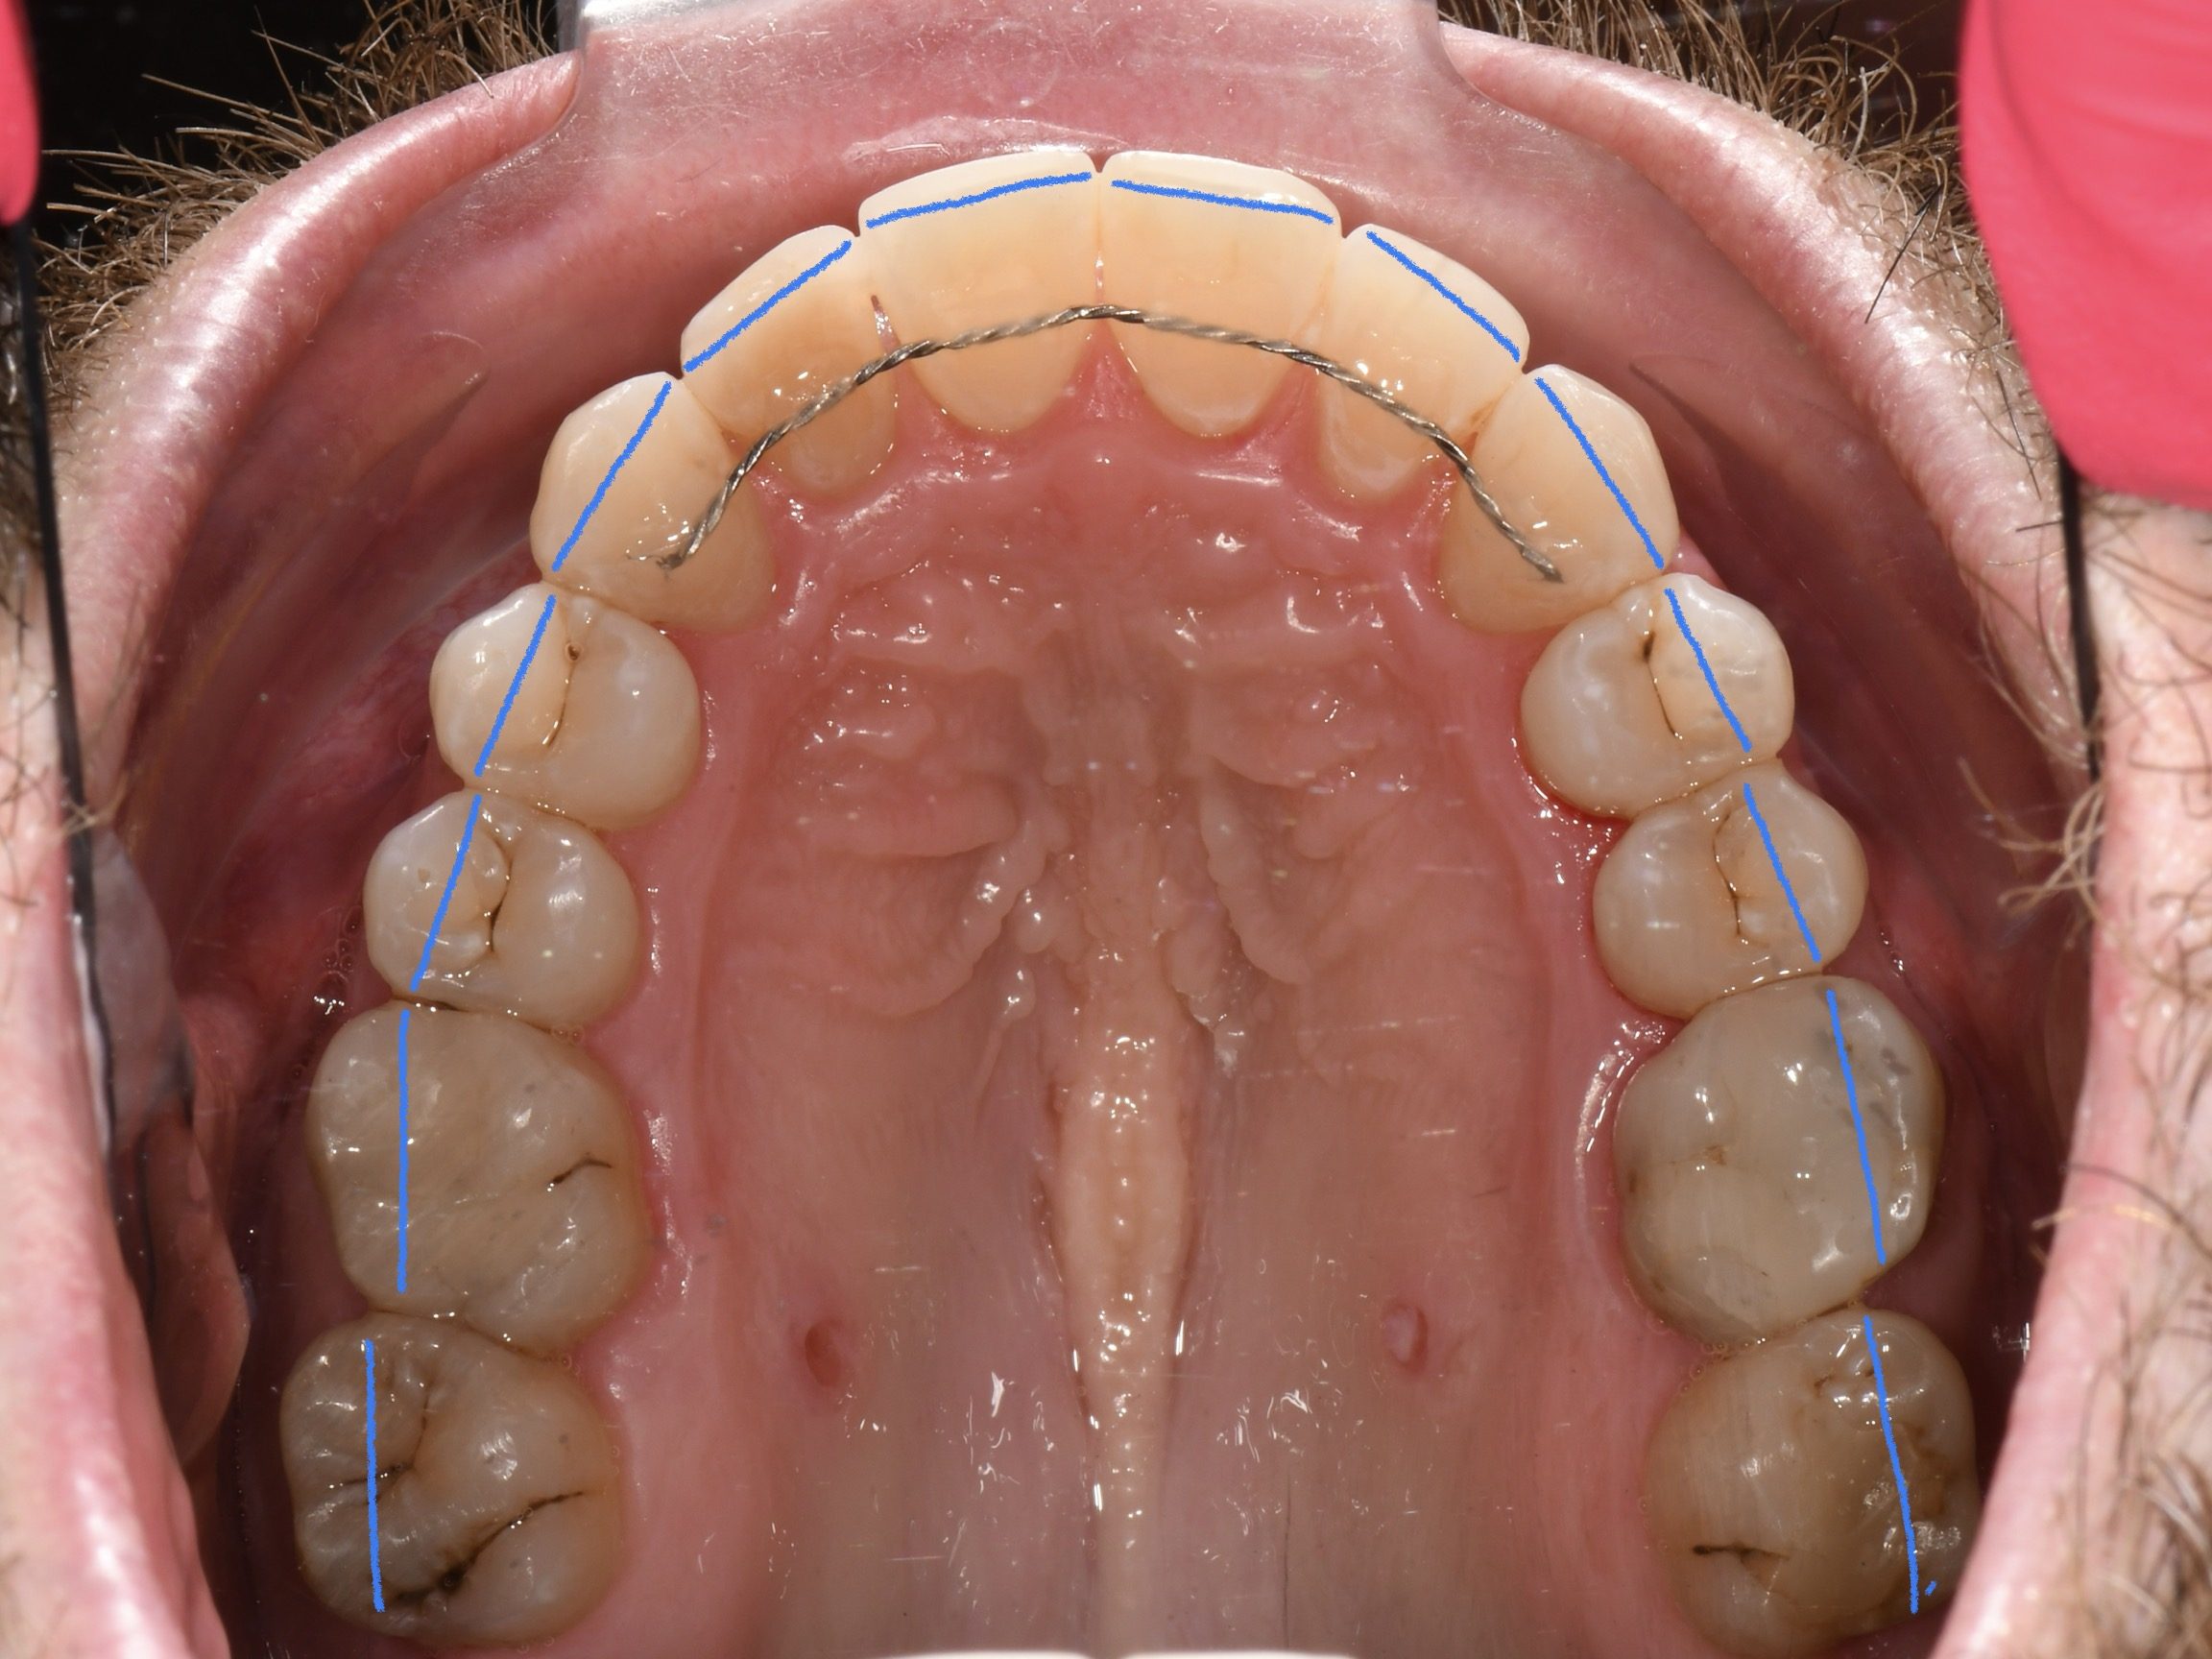

Az elmúlt évekből rengeteg szakmai referenciát tudnánk bemutatni, amelyek különböző fogszabályozási problémákat oldottak meg. Válogatva a több száz esetből, ezen az oldalon olyan képeket, információkat igyekeztünk bemutatni, amelyeknek a segítségével a jövőbeni pácienseinknek azt tudjuk üzenni: A Te fogsorod is lehet gyönyörű!

(Képeket a Pácienseink külön írásos beleegyezésével mutatjuk be!)